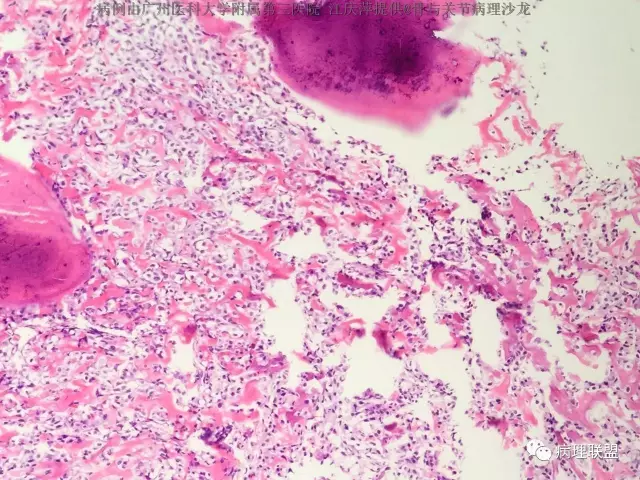

女,63,反复髋关节疼痛30年,活动受限2周(病例由广州医科大学附属第三医院 江庆萍提供,致谢)